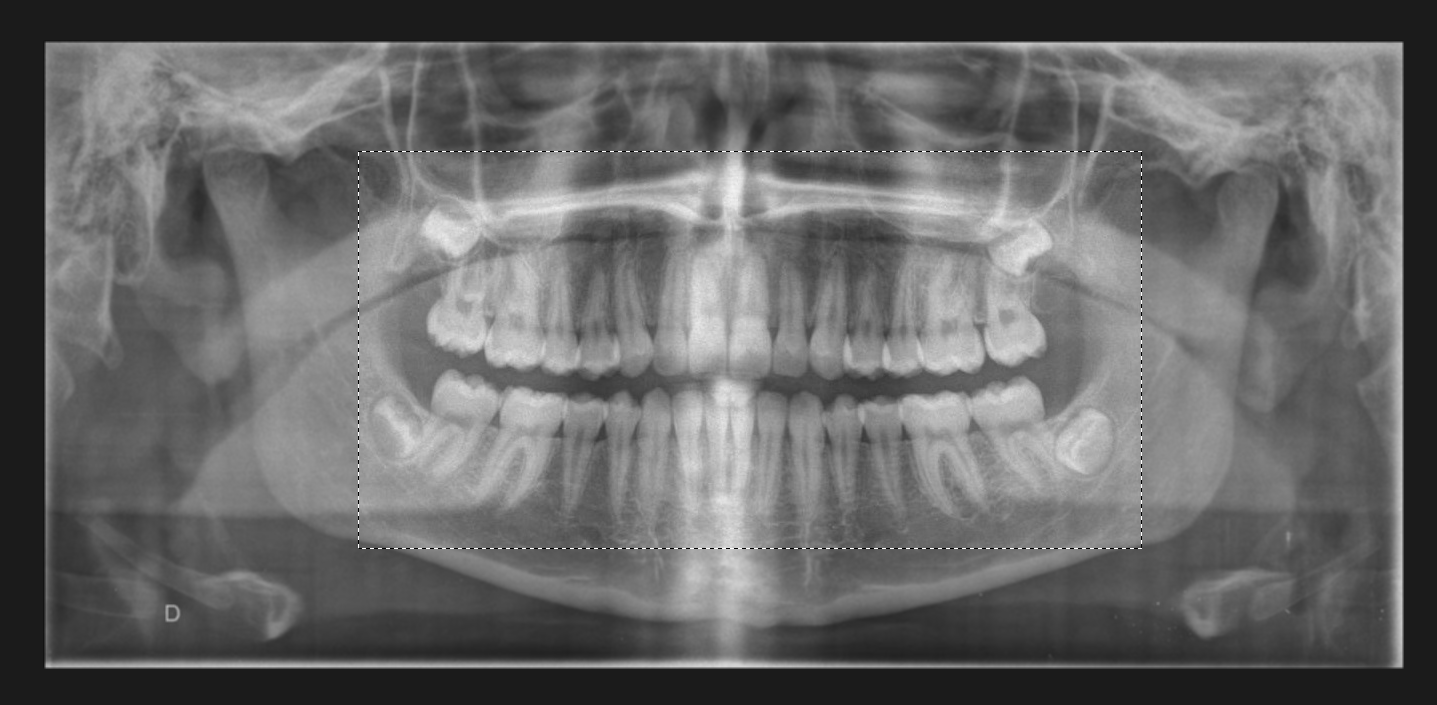

Cum funcționează? . Imaginați-vă că urmăriți un radio panoramic și doriți să capturați doar o zonă a acestuia. Apăsați butonul F6 al tastaturii (dacă este tasta corectă definită) și ecranul dvs. se va încețoșa imediat. Cu ajutorul mouse-ului, definiți un dreptunghi de captură și când eliberați butonul stâng al mouse-ului, captura va fi generată.

Zona selectată va deveni o fotografie nouă în dosarul pacientului. În acest fel, puteți captura fotografii, text, un tabel Excel sau ceea ce vedeți pe ecran.